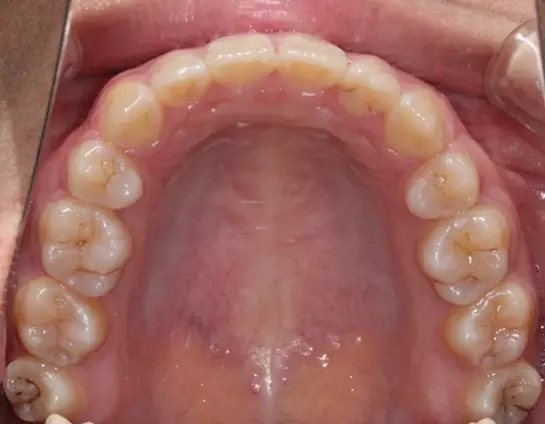

Damon 病例分享:安氏 II 類二分類露齦笑的矯治(董一磊)

治療前后對比